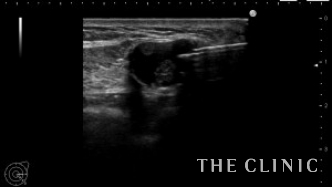

左乳腺下にオイルシストが2個ありました。

エコー下に穿刺吸引しました。

白濁したオイルが引けました。この後、コンデンスリッチ豊胸を行いました。